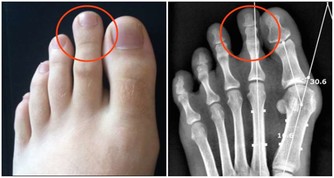

2. “太衝穴”在大腳趾與二腳趾分叉處的凹陷中。